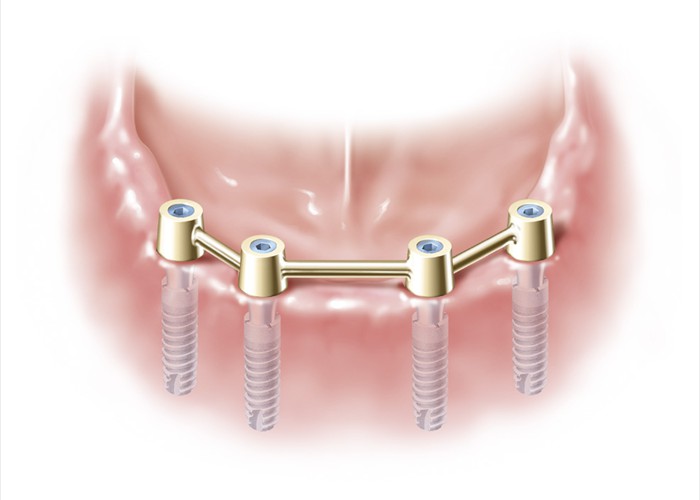

Vier durch Stege verbundene Implantate zur Stabilisierung der herausnehmbaren Teleskopprothese

Vier durch Stege verbundene Implantate zur Stabilisierung der herausnehmbaren Teleskopprothese